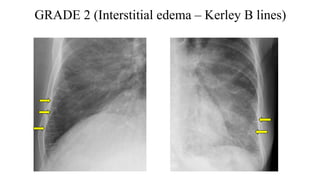

GRADE 2 (Interstitial edema – Kerley B lines)

II Interstitial edema Kerley B lines

GRADE 2 (Interstitialedema – Kerley B lines)